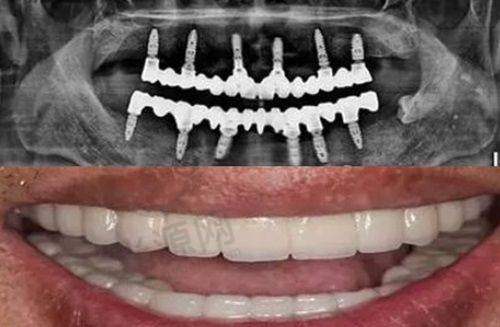

上海鼎植口腔是国内有名的连锁牙科机构,在国内多个城市都设有分院,仅在上海就有多家分店。该连锁以高难度种植牙为特色,拥有VIIV缺骨植技术(穿颧穿翼种植牙技术)、微创种植技术、3D数字化导板种植技术等精良技术。其种植牙价格相对实惠,和同资质牙科机构相比,性价比颇高,不少患者都对其种牙服务给予了高度评价。

华医生的特色项目包括种植牙失败修复、VIIV穿颧种植、VIIV穿翼板种植、TPP翼板种植、TPP颧骨种植、局麻下改良颌外颧骨种植等。他种牙速度快,穿颧穿翼种植牙颗数多,技术娴熟,口碑评价高,还经常被邀请去其他医院给医生做穿颧穿翼种植培训。他坐诊于鼎植黎强口腔门诊部、鼎植八八口腔门诊部。